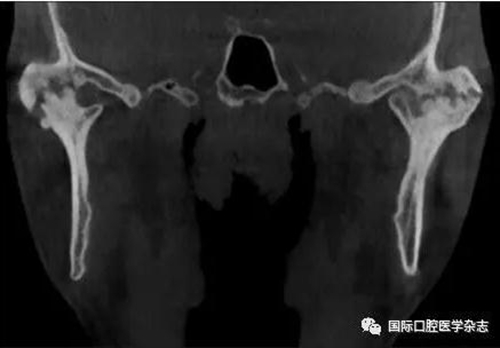

(4)關節(jié)強直(圖3):指因器質性病變導致長期開口困難或完全不能開口??煞譃殛P節(jié)內強直和關節(jié)外強直。關節(jié)內強直是由于一側或兩側關節(jié)內發(fā)生病變,造成關節(jié)內的纖維性或骨性粘連,也有人稱為真性關節(jié)強直。關節(jié)外強直是病變位于關節(jié)外上下頜間皮膚、黏膜或深層肌肉組織,形成頜間瘢痕攣縮(圖4),也有人稱為假性關節(jié)強直[7]。5)顳下頜關節(jié)感染:常由下頜關節(jié)附近化膿性病灶所致。多見于兒童中耳炎、腮腺炎等。此外還可由全身性傳染性疾病如麻疹、猩紅熱等引起。6)顳下頜關節(jié)外傷(圖5):外傷是引起開口受限的常見因素之一,最常見于下頜骨髁突骨折引起下頜運動受限[8]。

圖 3 關節(jié)內強直